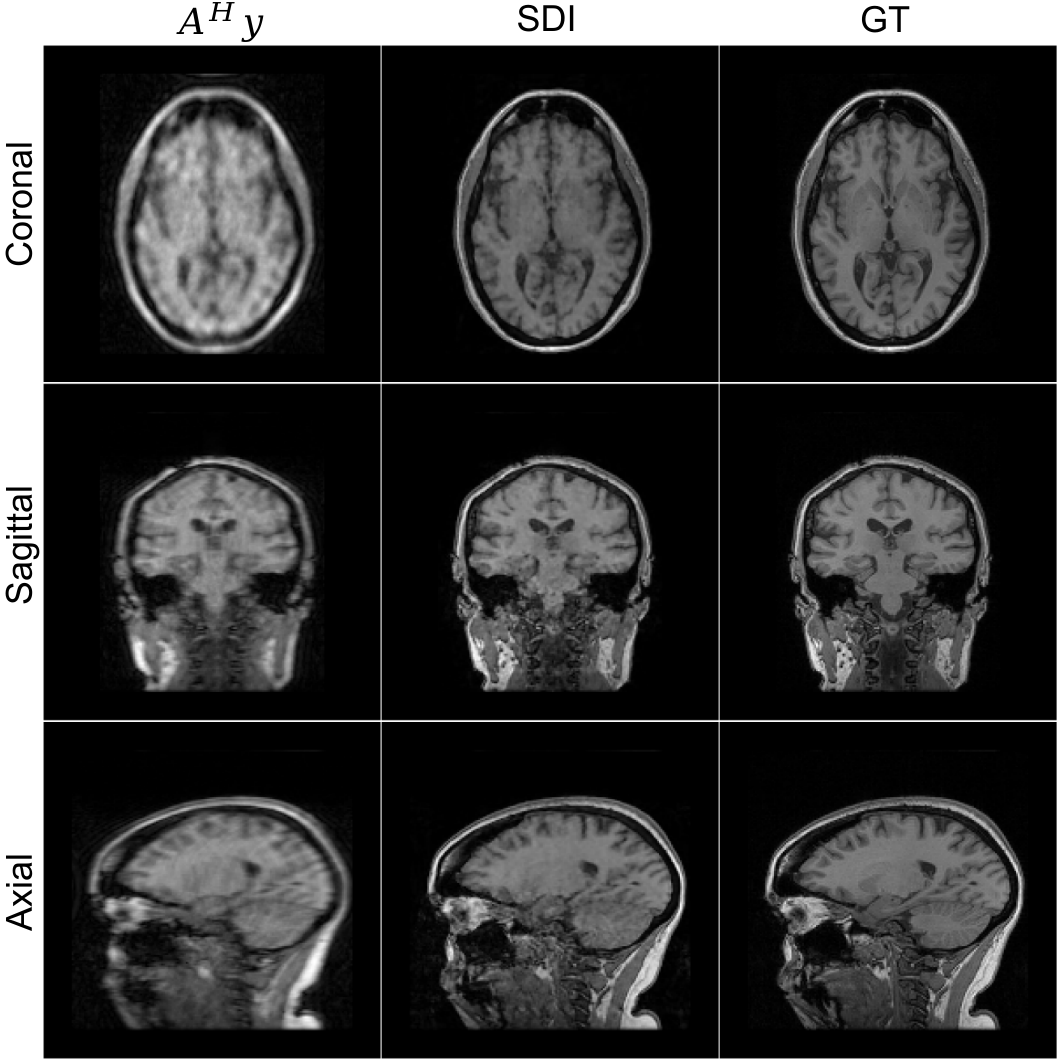

To further demonstrate the flexibility of self-diffusion, we apply it to the reconstruction of volumetric 3D MRI data from undersampled k-space measurements. This task poses additional challenges due to the increased dimensionality and the need for spatial coherence across slices. We consider a 12-coil 3D T1-weighted brain scan and apply a Cartesian undersampling mask on the k-space that has a dimension of 160×\times160×\times128. The undersampling mask is generated using BART’s command poisson with an acceleration factor of 2.5 along two phase-encoding directions. This leads to a total acceleration factor of 8. The coil sensitivities are estimated using BART’s command ecalib. The measurements 𝐲\mathbf{y} are formed with 𝒜\mathcal{A}, which consists of the undersampling mask, 3D Fourier transform, and coil sensitivities. To accommodate 3D dimensionality, we adapt the denoising network to a 3D U-Net architecture with 3D convolutional layers and which is initialized in the same way as the 2D U-Net. The parameters for Algorithm˜1 are {T=40;K=50;η=0.001}\{T=40;K=50;\eta=0.001\} and Adam optimizer is used. Figure 9 shows the reconstructed sagittal, coronal, and axial slices.

Figure 9: Reconstruction of a 3D T1-weighted brain MRI using self-diffusion from 8×\times undersampled measurements. Shown are sagittal, coronal, and axial slices, demonstrating sharp anatomical structures and minimal artifacts. The initial measurement (𝒜H𝐲\mathcal{A}^{H}\mathbf{y}), self-diffusion inference (SDI), and ground truth (GT).